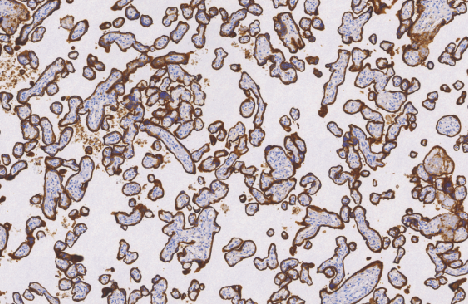

CD71鼠抗人CD71单克隆抗体

CD71分子是II型膜糖蛋白分子量大约为180KD。CD71被认为是铁传递蛋白受体并由两个二硫化物组合的90KD亚单位组成。CD71分子在细胞增生中通过控制铁的提供起关键作用,这是许多代谢旁路的基础组成,通过结合与细胞内吞噬铁转运蛋白,主要是铁携带蛋白。据报道CD71蛋白表达在活化B细胞和T细胞,巨噬细胞增生细胞和代谢活跃的细胞如神经元中。

- 阳性部位:胞质,胞膜

- 适用组织:石蜡切片

- 预处理:热修复